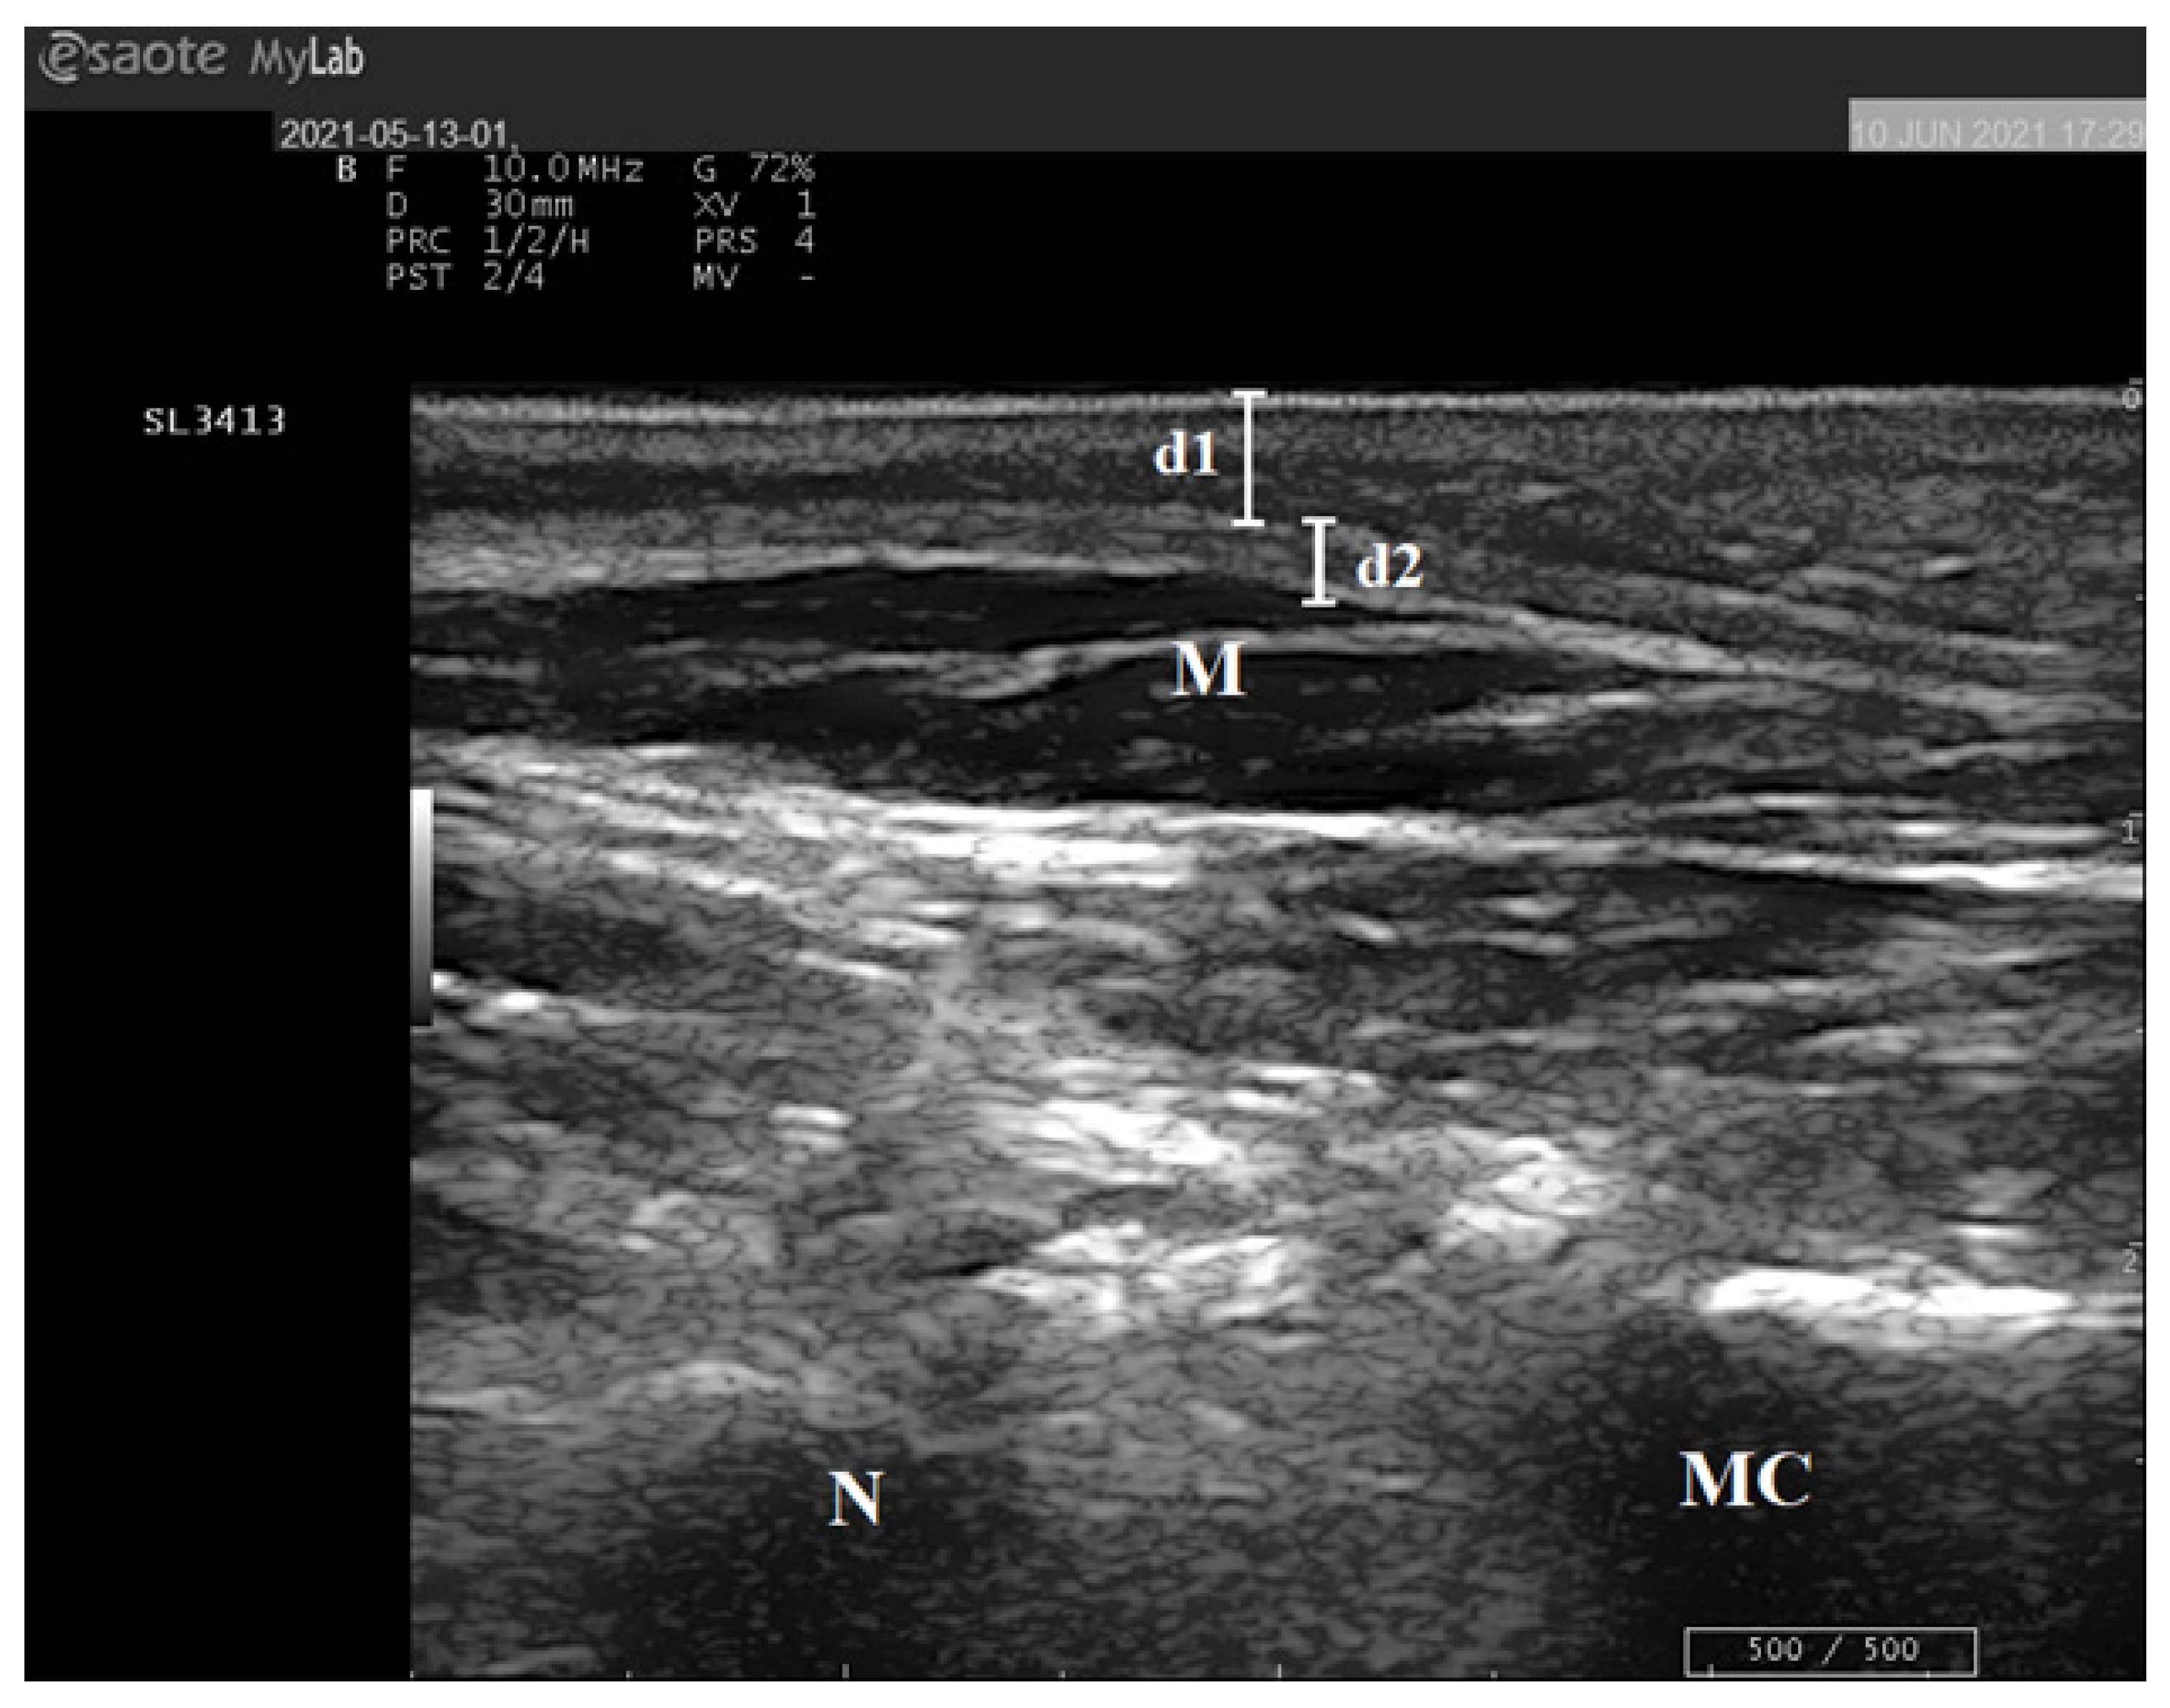

2.4. Ultrasound Examination of the Foot